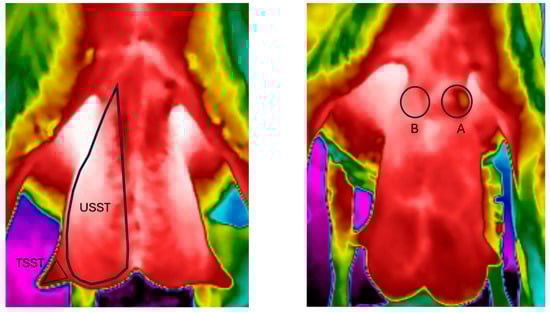

3.2. Thermal Image Analyses—Temperature Values

3.2.3. Skin Surface Temperature at the Abscess Site